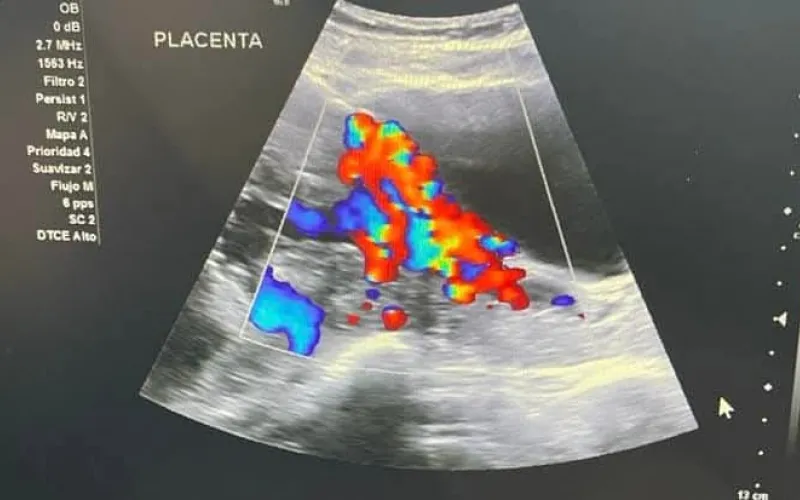

Chacón Lechuga indicó que la mayoría de los casos atendidos son por acretismos placentarios en sus tres niveles: acreta, percreta e increta, es decir, que la placenta está adherida de una manera anormal a la matriz, a otros órganos y a los vasos sanguíneos, lo que puede provocar una hemorragia severa.